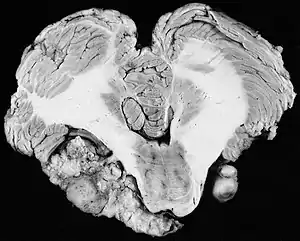

Bilateral schwannomas in a patient with neurofibromatosis 2

Neurofibromatosis Type 2 (NF2)

For the most part, unilateral sporadic vestibular schwannomas are readily treated successfully by modern medical techniques. Having bilateral VSs is a more troublesome condition. Bilateralism is considered to be the hallmark and main diagnostic criterion of Neurofibromatosis Type II (NF2), a genetic disorder that is heritable, progressive, difficult to manage, and has a 1 in 2 chance of being passed on to each offspring. NF2 patients tend to have a more severe mutation, although there are mild mosaic cases in which only some cells carry the mutation. Genetic testing confirming mutation of the NF2 gene is recommended. About 50% of people with NF2 have a de novo mutation, and about 50% of these new mutations will be mild mosaic cases which are less likely to be passed on. NF2 patients may develop other cranial and spine tumors. NF2 develops during the teens or early adulthood, whereas sporadic VSs are diagnosed mostly in patients between the ages of 40–60 years. Both varieties of VS (sporadic and NF2) are very rare, accounting for only about 8% of all primary brain tumors. The incidence of NF2 is approximately 1 per 60,000 people.[6][7][8]